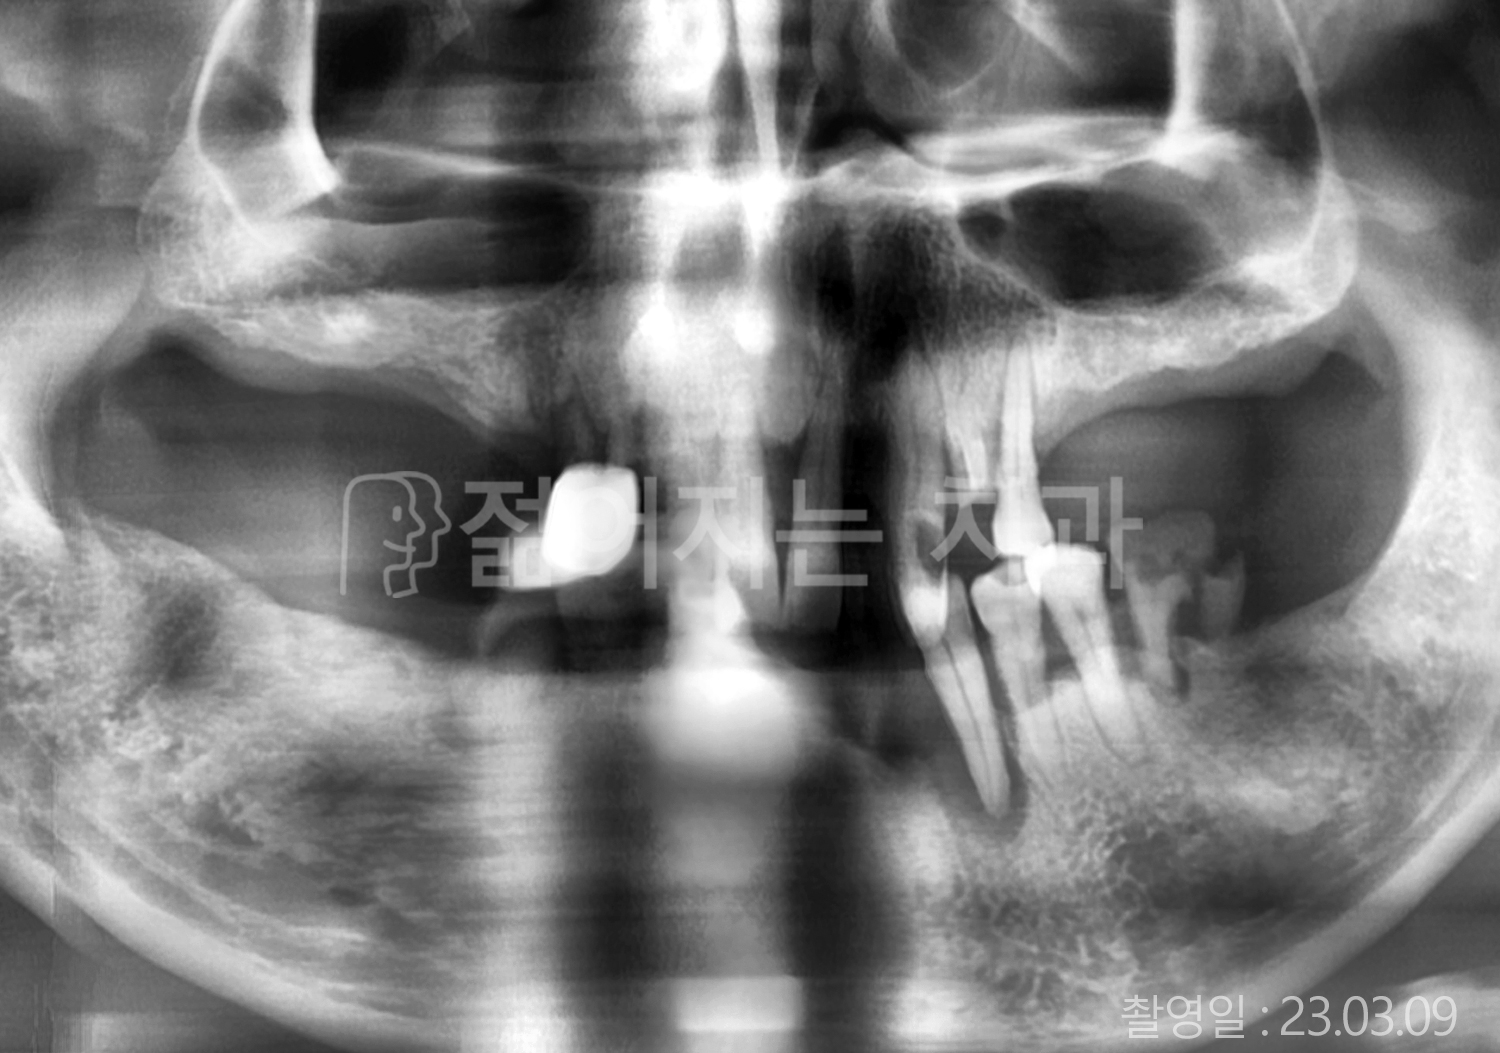

• 60대 전체치아 10개 이상 임플란트